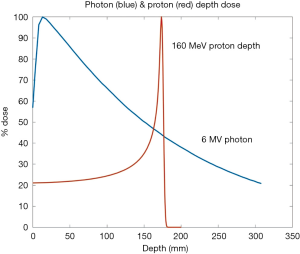

This is even more important for proton therapy, due to the sharp dose fall-off at the end of the Bragg peak (10-12), which will be described in more detail in the following section.

The promise of proton therapy lies heavily on the existence of a Bragg peak, a narrow region where the dose deposition peaks and falls off sharply as shown in Figure 2. Protons with higher energies deposit their maximum dose at greater depths. By accumulating weighted dose depositions over a range of proton energies, a spread-out Bragg peak (SOBP) can be obtained. This is shown in Figure 3, where the proportion of proton fluence with energies 139, 137, 131, and 125 MeV are 0.32, 0.28, 0.23 and 0.17 respectively. Using more energies between the range 125 to 137 MeV, a more uniform “flat top” depth dose can be attained. By designing proper beam entries, a very conformal dose distribution can be achieved using proton therapy, with sufficiently coverage of the clinical tumour volume (CTV), and minimal dose to the OARs which are beyond the range of the maximum energy protons (16,17). An example is as shown in Figure 4.